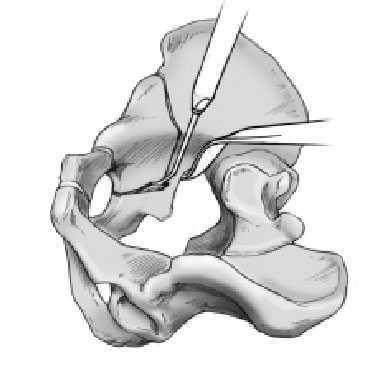

Figura 14 Primer paso de la tercera osteotomía. La tercera osteotomía transcurre a través del hueso isquion y se completa en dos pasos. El primer paso transcurre la osteotomía anterior por debajo del acetábulo (fig. 17). El abordaje para esta osteotomía se realizará bien medial o bien lateral respecto al músculo psoas dependiendo de cual de los dos abordajes proporcione mejor visión. Se coloca un separador de Klaue en el borde anterior del hueso isquion dentro del agujero obturador y se gira en el sentido de las agujas del reloj en la cadera derecha o en sentido contrario en la cadera izquierda. Se dirige el escoplo curvo angulado 35º desde la entrada de la pelvis con su lado cóncavo hacia la lámina cuadrilátera del acetábulo. Cuando el ángulo del osteotomo se apoye en el borde del hueso y el mango este perpendicular a la entrada de la pelvis, la línea de osteotomía se hallará a 4 cm de la entrada de la pelvis. Entonces la punta anterior del escoplo debe manipularse sobre el reborde anterior del isquion hacia el agujero obturador. El mango del escoplo debe manipularse en la superficie dorsal del acetábulo

en el sentido de las agujas del reloj en la cadera derecha y en el sentido contrario en la cadera izquierda. Esta maniobra debe repetirse varias veces, para garantizar una posición correcta

del escoplo. Debe asegurarse el mantener una distancia de 4 cm. Si la osteotomía se localiza demasiado distal, la movilización del acetábulo se hace dificultosa. Si se hace demasiado proximal hay riesgo de una lesión de la articulación. Se comprobará por eso la localización del escoplo mediante escopia, mientras se sostiene el mango del escoplo perpendicular a la entrada de la pelvis. En caso de posición correcta se introduce el escoplo 1 cm en el hueso hasta que el mismo sostenga dicha posición. Se secciona entonces la parte anterior del isquion.

Figura 15 Segundo paso, tercera osteotomía. Es el que conecta la osteotomía ya realizada de la columna posterior hasta la osteotomía anterior del isquion. El escoplo curvo se colocará lateral o medial al músculo psoas. El mango del escoplo se mantiene perpendicular a la inclinación de la entrada de la pelvis. La línea de osteotomía debería localizarse 4 cm por debajo de la entrada de la pelvis, es decir, de la línea innominada. Esta distancia se medirá con el escoplo. Esta osteotomía debería iniciarse en el punto final de la columna posterior (osteotomía del isquion). Esta osteotomía se realizará en sentido distal, de medial a lateral con un ángulo de 35º. El escoplo se introducirá aproximadamente 1 cm en el isquion, siempre manteniendo el mango perpendicular al plano de la entrada de la pelvis. Este procedimiento se repetirá hasta completar la osteotomía del isquion.